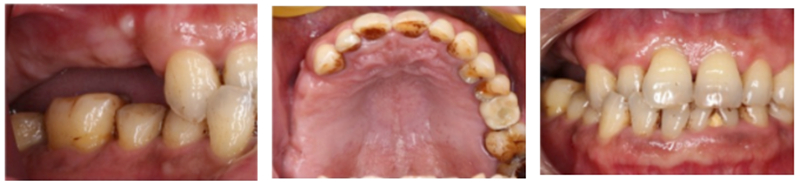

主訴:右側后牙缺失6個月以上,要求種植修復。

現(xiàn)病史: 多顆后牙連續(xù)缺失,未進行活動修復 。

檢查:患者14、15、16、17缺失,無紅腫潰瘍,牙齦情況良好,口腔衛(wèi)生狀況良好。

診斷:14、15、16、17缺失

處理:通過數(shù)字化種植導航進行15、16、17種植修復

®石膏模型上進行排牙確定患者咬合關系,取放射阻射材料灌于缺牙區(qū),患者戴著處理過的

配準裝置拍攝術前CBCT。

®根據(jù)CBCT中牙冠顯影位置,按照修復引導種植的原則進行方案設計